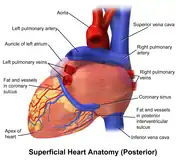

The heart has four chambers, two upper atria, the receiving chambers, and two lower ventricles, the discharging chambers. The atria open into the ventricles via the atrioventricular valves, present in the atrioventricular septum. This distinction is visible also on the surface of the heart as the coronary sulcus.[20] There is an ear-shaped structure in the upper right atrium called the right atrial appendage, or auricle, and another in the upper left atrium, the left atrial appendage.[21] The right atrium and the right ventricle together are sometimes referred to as the right heart. Similarly, the left atrium and the left ventricle together are sometimes referred to as the left heart.[6] The ventricles are separated from each other by the interventricular septum, visible on the surface of the heart as the anterior longitudinal sulcus and the posterior interventricular sulcus.[20]

Heart tissue receives blood from two arteries which arise just above the aortic valve. These are the left main coronary artery and the right coronary artery. The left main coronary artery splits shortly after leaving the aorta into two vessels, the left anterior descending and the left circumflex artery. The left anterior descending artery supplies heart tissue and the front, outer side, and septum of the left ventricle. It does this by branching into smaller arteries—diagonal and septal branches. The left circumflex supplies the back and underneath of the left ventricle. The right coronary artery supplies the right atrium, right ventricle, and lower posterior sections of the left ventricle. The right coronary artery also supplies blood to the atrioventricular node (in about 90% of people) and the sinoatrial node (in about 60% of people). The right coronary artery runs in a groove at the back of the heart and the left anterior descending artery runs in a groove at the front. There is significant variation between people in the anatomy of the arteries that supply the heart [32] The arteries divide at their furthest reaches into smaller branches that join at the edges of each arterial distribution.[7]

The coronary sinus is a large vein that drains into the right atrium, and receives most of the venous drainage of the heart. It receives blood from the great cardiac vein (receiving the left atrium and both ventricles), the posterior cardiac vein (draining the back of the left ventricle), the middle cardiac vein (draining the bottom of the left and right ventricles), and small cardiac veins.[33] The anterior cardiac veins drain the front of the right ventricle and drain directly into the right atrium.[7]